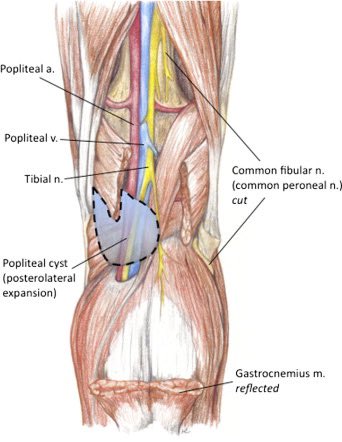

Expanding Baker's cyst causes edema in the lower limb.

#vascularultrasound

search.app/yb3sVUUGve7Kx2…